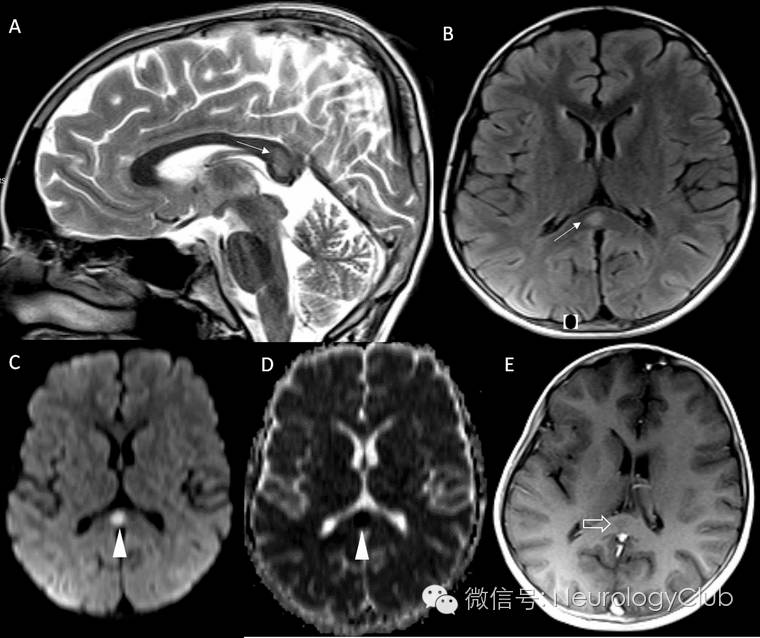

(图2:腮腺炎病毒感染相关的RESLES。起病时的MRI上可见SCC病灶[A-C依次为ADC,DWI和FLAIR],2周后复查病灶消失[D,DWI])

(图3:激素治疗相关的RESLES。A:T2WI高信号;B:FLAIR高信号;C:DWI高信号;D:ADC低信号;E:T1增强未见病灶强化;3周后病灶消失

磁共振是诊断RESLES的首选检查。其特征性的影像学表现为SCC(一般位于中心区域)局限性的椭圆形或条状的病变,如出现整个胼胝体压部受累的条状病变,称为“回旋镖征”(Boomerang sign)。病灶于T1WI上呈等或低信号,T2WI/FLAIR和DWI上均为高信号,ADC值降低,增强扫描无明显强化。目前尚无胼胝体压部发生囊病或坏死的报道。病变可不仅仅局限在胼胝体压部,其他部位如膝部、体部也可同时出现,甚至可以累及胼胝体外,如脑室旁白质,皮质下白质和基底节区,而这些病灶基本上也是可逆的。最近的研究表明,胼胝体外病变的出现往往提示预后不良,而胼胝体其他部位是否出现病灶与预后并无明显联系。各种病因导致的RESLES影像学异常和消失的时间如表1所示。